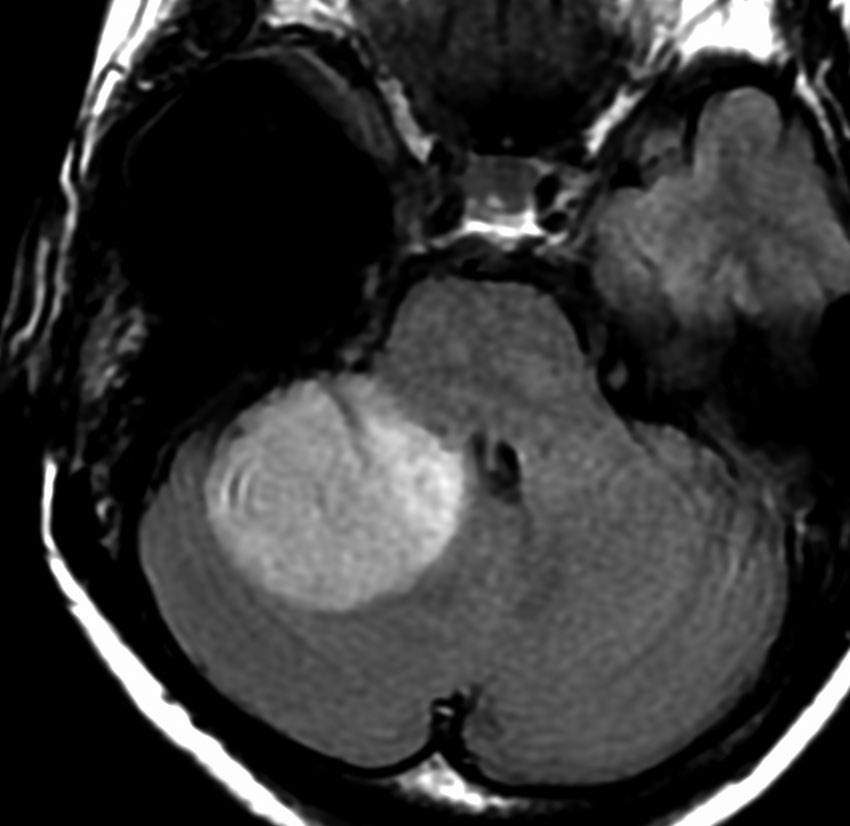

35歳,側頭葉てんかんで発症した右側頭葉の乏突起膠腫 グレード2です。全摘出して化学療法4コースと54グレイの局所放射線治療 generous local fieldを行いました。7年後に同じ部位に再発して摘出したところ退形成性乏突起膠腫 グレード3となっていました。手術摘出して,テモゾロマイド化学療法で維持療法をしていました。

その2年後の画像です。右小脳半球に再発しています。右側頭葉腫瘍との連続性は全くありませんでした。脳幹部にも腫瘍はありません。遠隔再発 remote recurrenceというもので,星細胞系腫瘍 astroytic tumor AAやGBMではよく知られている現象です。乏突起膠細胞系腫瘍でもまれにみられます。

だからと言って初期治療で広範囲放射線治療をした方がいいということにはならず,これを避ける手段はありません。